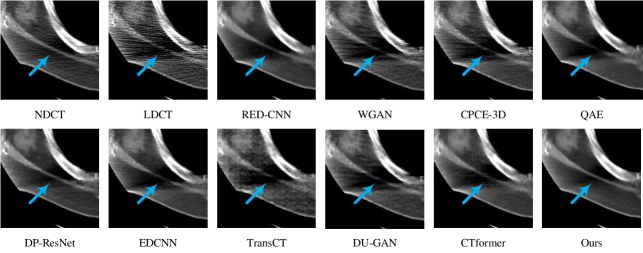

Refer to caption

Figure 10: Illustration of the two samples, where the box regions in red were identified as (a) Metastasis pancreas and (b) Aorta. Their zoom-in comparisons are presented in Figs. 11-12. (WL: 10, WW: 400)

Figure 11: Zoom-in visualization of the red box region in Fig. 10(a). The low-contrast lesion is marked by the yellow arrow (Slice ID: L593-050, WL: 10, WW: 400, source of diagnosis: the AAPM Grand Challenge committee).

Figure 12: Zoom-in visualization of the red box region in Fig. 10(b). The yellow arrow marks the uniformly distributed aorta (Slice ID: L548-050, WL: 10, WW: 300).

Interestingly, RED-CNN, DP-ResNet, and TransCT received high noise suppression scores but low margin sharpness scores due to aggressive denoising (i.e., over-smoothing). On the contrary, the introduction of detail preservation constraints (e.g., perceptual loss in CPCE-3D and adversarial loss in WGAN and DU-GAN) led to compromised denoising performance and reduced diagnostic sensitivity. In comparison, the proposed method can reach a pleasing balance between these aspects, yielding satisfactory results that radiologists prefer.

Last, we show two representative examples from these evaluations: Fig. 10 presents an overview of the two samples in full-dose, in which their zoom-in crops are compared in Figs. 11-12: Fig. 11 depicts a lesion that is barely noticeable by experts due to its low contrast. Similar to the full-dose references, our method could transfer details more faithfully and maintain the contrast but with an even lower noise level. In comparison, some methods either failed to suppress noise (e.g., WGAN, DU-GAN) or introduced artifacts (e.g., CTformer), making them less reliable in clinical exams. Fig. 12 visualizes the cross-section of the aorta, where the higher uniformity in our result indicates better denoising quality.